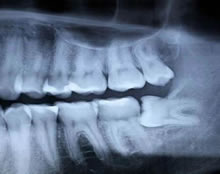

The dentist will be able to assess whether there is sufficient room for the teeth to come through by taking an x-ray which will show the position of the root. Once the x-rays have been taken, the dentist will be able to tell how easy or difficult it will be to remove the tooth. The dentist will then determine whether the tooth should be taken out by an oral surgeon or a Dental Surgeon with Oral Surgery experience.